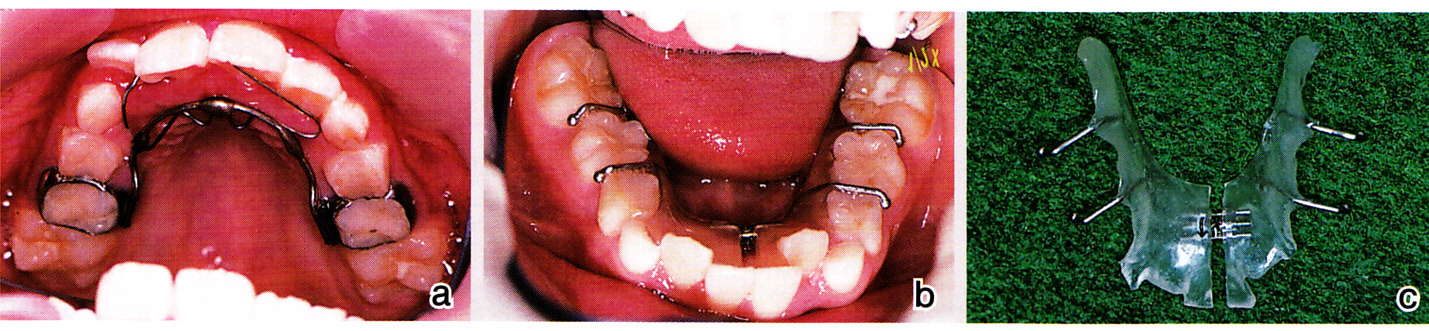

「よく噛む」だけではとても解決しないと思われたため、上下顎に装置を入れて介入を始めました。下顎にはエクスパンジョンスクリューを持つ拡大床を装着し、ねじを週に1回(0.25㎜)広げるよう指示しました(図12)。

図12 a:8歳 上顎・・・・リンガルアーチで上下左右1番の反対咬合を改善する

b・c:8歳 下顎の叢生は拡大床で改善する。拡大のペースは週に1回0.25㎜